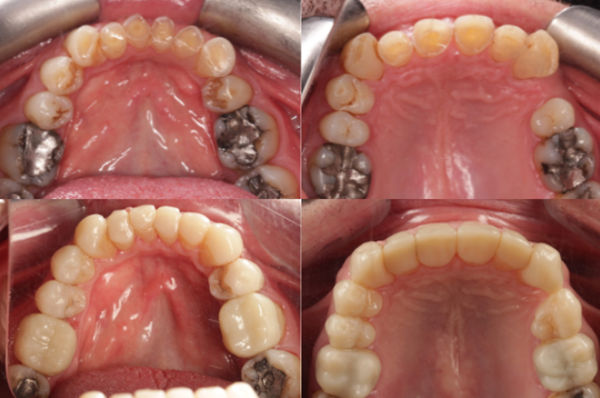

從左到右、從上到下,3D打印技術(shù)幫助減輕了患者的嚴(yán)重牙齒磨損。

加哈爾醫(yī)生采用以患者為中心的治療方法,與患者討論治療目標(biāo),包括保護(hù)剩余牙體組織、恢復(fù)垂直咬合距離(閉合時上下頜之間的自然距離)以及改善美觀,同時盡可能減少治療創(chuàng)傷。該患者的病例存在諸多挑戰(zhàn),包括臨床牙冠(牙齦線以上的牙齒可見部分)嚴(yán)重縮短,牙髓幾乎完全暴露;牙槽代償(牙齒磨損導(dǎo)致的頜骨位置改變,可能影響咬合);牙齦根尖不對稱(牙齦高度不均,影響微笑線);以及犬齒頰側(cè)偏位(牙齒向外傾斜)。所有這些因素都需要精心規(guī)劃,才能達(dá)到自然且功能完善的治療效果。

整個修復(fù)過程采用全數(shù)字化流程,首先制作診斷蠟型,即用于可視化牙齒預(yù)期形狀和位置的數(shù)字或?qū)嶓w模型。然后使用雙丙烯酸樹脂(一種臨時材料)將其轉(zhuǎn)化為“試戴微笑”,以便患者預(yù)覽擬定的設(shè)計方案。試戴微笑使患者有機(jī)會在進(jìn)入下一階段之前確認(rèn)預(yù)期的咬合、美觀和發(fā)音效果。設(shè)計方案獲得批準(zhǔn)后,最終的STL文件被發(fā)送到SprintRay Pro 2打印機(jī),用于制作永久牙冠。術(shù)后處理包括使用99%異丙醇進(jìn)行手工清潔、涂層、最終固化、拋光和微調(diào)。粘接過程需要精細(xì)的表面處理、底涂和在甘油下進(jìn)行最終固化,以確保最佳的密合度和長期的耐用性。